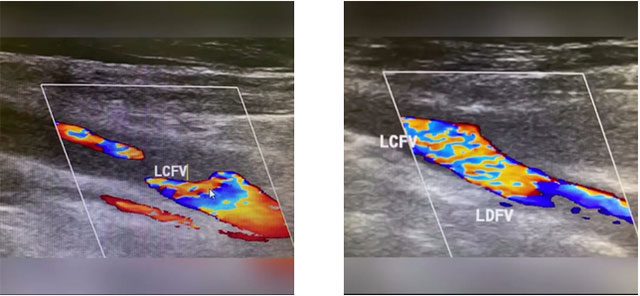

患者为56岁男性,患有高血压。入院时,脑出血术后,颅内静脉窦血栓术后,左侧肢体活动不利,左侧上肢肌力1级,下肢肌力1级。下肢彩超显示,久坐后左侧股总静脉、股浅静脉、股神静脉血栓形成,左侧腘静脉血流淤滞,CTA提示右下肺动脉下段栓塞。如不及时采取措施,血栓可能会进入患者肺部引起肺栓塞,从而危及生命。

▲ 彩超显示下肢深静脉血栓形成